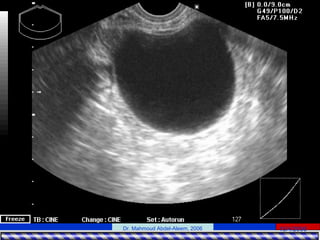

• Imaging

– TVS: it is a suitable screening test for

evaluation of the endometrial cavity.

• Timing: should be performed after menstruation in

the follicular phase of the menstrual cycle.

• Value:

– Sonohysterography is the sonographic

evaluation of the endometrial cavity following

the transcervical instillation of saline, an

approach that has comparable results for

structural anomalies of the endometrial cavity to

those of hysteroscopy.

– Radiographic hysterography is less accurate

than hysteroscopy for cavity evaluation.